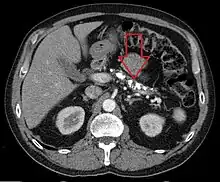

| Axial CT showing multiple calcifications in the pancreas in a patient with chronic pancreatitis | |

Computed tomography, magnetic resonance cholangiopancreatography (MRCP), and endoscopic ultrasound (EUS) all have similar sensitivity and specificity for diagnosing chronic pancreatitis.[3] MRCP is particularly utilized for its sensitivity in imaging the pancreatic ducts and bile ducts for associated changes such as stones or strictures.[3][12] A biopsy of the pancreas is not required for the diagnosis.[3] On imaging, pancreatic and bile duct dilatation, atrophy of the pancreas, multiple calcifications of the pancreas, and enlargement of pancreatic glands can be found.[12]